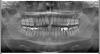

sofitt Опубликовано 13 мая, 2009 Поделиться Опубликовано 13 мая, 2009 Уважаемые специалисты, такой вопрос.Хочу поставить имплантант на место удаленной несколько лет назад правой верхней пятерки. При осмотре хирург солавшись на конвергенцию соседних зубов и недостаток места в связи с этим отказался это делать, при этом указал на необходимость предварительного ортодонтического лечения, другой хирург наоборот, сказал, что места действительно чуть маловато, но можно шлифануть эмаль на соседих здоровых зубах. На ортопантограмме видно нехватает два три мм. Что делать? Ссылка на комментарий

Orthodoc Опубликовано 14 мая, 2009 Поделиться Опубликовано 14 мая, 2009 Уважаемые специалисты, такой вопрос.Хочу поставить имплантант на место удаленной несколько лет назад правой верхней пятерки. При осмотре хирург солавшись на конвергенцию соседних зубов и недостаток места в связи с этим отказался это делать, при этом указал на необходимость предварительного ортодонтического лечения, другой хирург наоборот, сказал, что места действительно чуть маловато, но можно шлифануть эмаль на соседих здоровых зубах. На ортопантограмме видно нехватает два три мм. Что делать?На мой взгляд, необходимо провести ортодонтическую подготовку, этот метод более физиологичный, чем достаточно серьезная сепарация. Кроме того, по орто видно. что у Вас есть промежутки между зубами, их можно закрыть за счет смещения зубов. Ссылка на комментарий

Anvik Опубликовано 23 мая, 2009 Поделиться Опубликовано 23 мая, 2009 Доброе утро! Проблема на самом деле не так проста- для постановки имплантата в области малого жевательного зуба необходимо около 6 мм- 2мм по краям, от имплантата до корней соседних зубов + сам имплантат около 2 мм в диаметре, таким образом - или расширять имеющееся расстояние (но для этого может понадобиться удаление 8-го зуба сверху справа и смещение 7-го и 6-го назад с помощью миниимплантатов), или с помощью брекет системы закрыть это расстояние своими зубами. Но можно поставить и мост- что хуже, на мой взгляд. Ссылка на комментарий

Bier Опубликовано 28 мая, 2009 Поделиться Опубликовано 28 мая, 2009 имплантат 3,5мм +3-4мм (1,5-2мм с каждой стороны от имплантата) и того 7мм по любому надо иметь.Но в кости вроде есть эти 7мм. А вот коронки зубов немного сошлись. Но я все равно за ортодонтию. Ссылка на комментарий

Force Опубликовано 28 мая, 2009 Поделиться Опубликовано 28 мая, 2009 согласен с докторами: промежутки + прекрасное расстояние между КОРНЯМИ, наклон коронок - показание для ортодонтии... на оптг видна неслабая стираемость передних зубов, а это уже отдельная песня...... Ссылка на комментарий